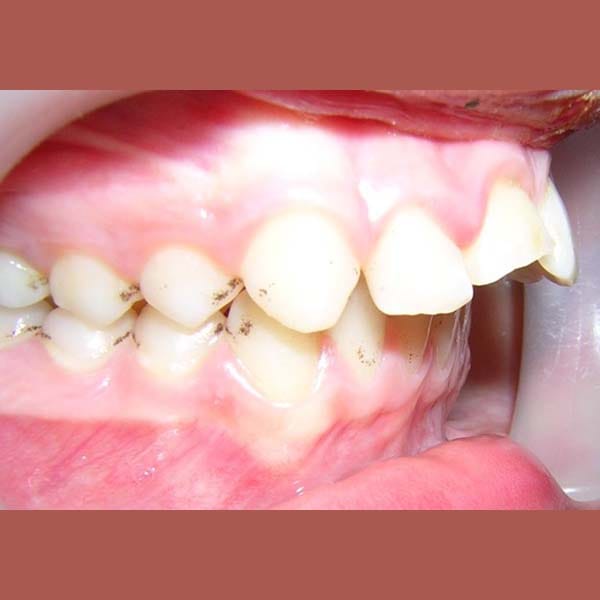

عانت هذه الفتاة الصغيرة من بروز شديد في الأسنان وصل إلى 1 سم، وكان سببه الرئيسي هو تراجع الفك السفلي، وهو ما كان يظهر بوضوح على بروفيل وجهها الجانبي.

كما تظهر الصور، كان التحسن جذرياً ليس فقط في الابتسامة ولكن في تناسق ملامح الوجه بالكامل. تم تصحيح البروز، وتحسنت علاقة الفكين، وحصلت صديقتنا الصغيرة على ابتسامة جميلة وواثقة.